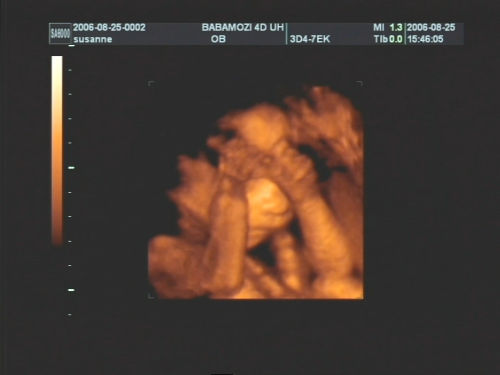

Pár kép:)

És akkor jöjjenek a képek:

Nem tudtam betelni velük,és nem tudtam választani közülük,azért van ilyen sok:

Kép Olyan kis szégyellős volt a drága,hogy állandóan takargatta a szemeit:Kép

És akkor az egyértelmű jelek:

Kép